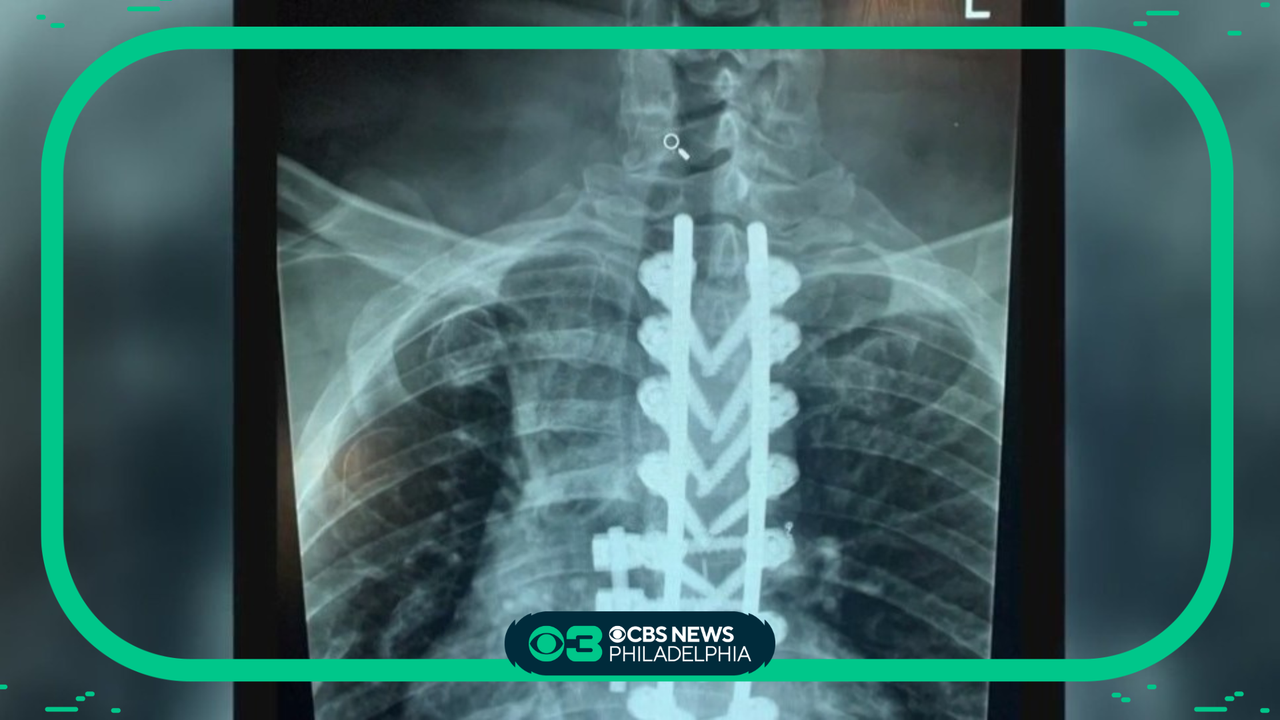

How botox is being used to treat a unique muscle spasm

Stephanie Stahl reports.